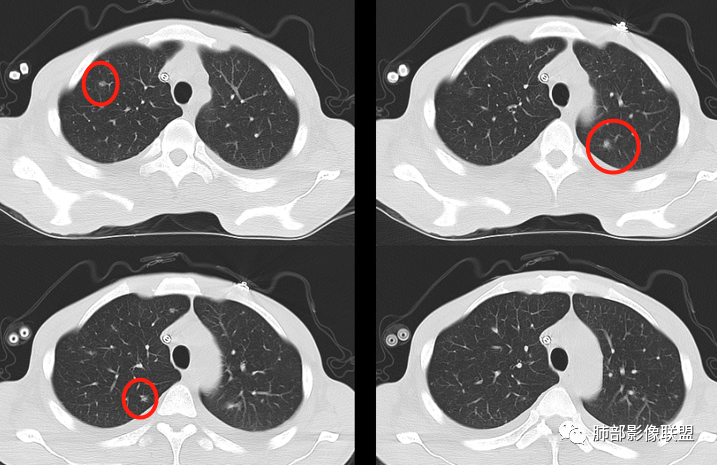

2、两肺多发结节,中上肺分布为主,结节边界尚清,部分边界平直

3、左上叶下舌段见沿支气管走形斑片状高密度影,边界模糊

从整体表现,结节的边缘、形态,片状影的改变——支持炎性

2.双肺散在不规则小片状影及结节影,部分可见磨玻璃晕。结节影边界较清楚。左肺片影边界不清,范围较大,支气管相关,支气管壁增厚不明显,病灶内见液化空洞。

2)病灶大多随机分布,磨玻璃晕等,没有新旧不等,且两个月内出现这样病灶,肺结核的可能性非常小。

3)有恶性肿瘤病史及治疗史,血糖高,属易感人群,两个月内出现片影及肉芽肿样结节影且带磨玻璃晕,出现空洞的,是应当考虑到侵袭性肺真菌病的,如常见的侵袭性肺曲霉病等。注意,这应当是易感人群真菌感染的较为经典的时间段!

3.肺炎型肺部影像学表现常为双肺多发片影,肉芽肿样结节影,边界相对清楚,可见磨玻璃晕,部分病灶可显示坏死空洞。部分病例出现胸水。支气管炎型病例可见较广泛支气管壁增厚。

单就肺部影像学表现而言,有时与其他一些真菌感染如曲霉病并不好区分。

有统计表明,干细胞移植患者双肺常以肉芽肿结节为主要表现。